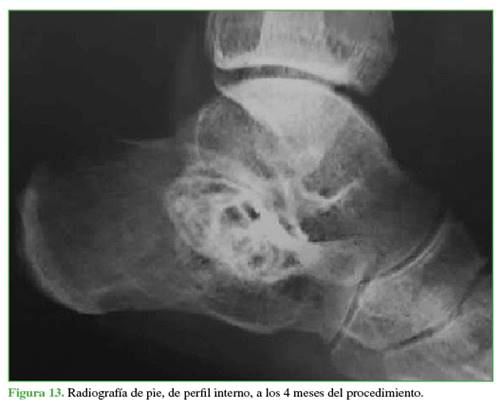

En los sucesivos controles clínicos y radiológicos, se comprobó la osificación de los quistes y la desaparición del dolor (Figuras 13-15). Después de más de 2 años de seguimiento, el paciente no ha vuelto a consultar. Como se sabe que el QOA puede recidivar, se debe mantener un control a más largo plazo.